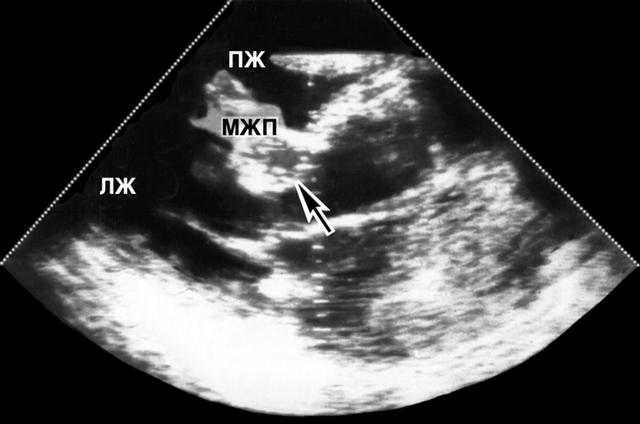

Рис. 4а). Двухмерная эхокардиограмма больного с обструктивной гипертрофической кардиомиопатией: ПЖ — правый желодочек, МЖП — межжелудочковая перегородка, ЛЖ — левый желудочек.